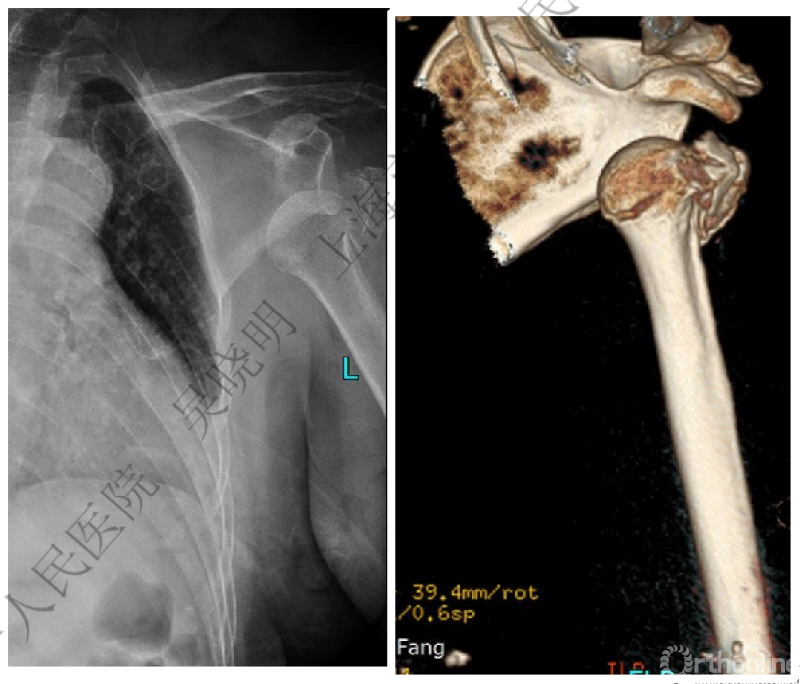

警惕孤立性向下移位的大结节骨折

外翻压缩型肱骨近端骨折

钢板固定

X线是孤立性向下移位的大结节,一定要小心,多伴有肱骨外科颈骨折

肱骨解剖颈伴大结节骨折的老年性肩关节前脱位

切开复位

VS

闭合复位

全麻下闭合复位,钢板固定